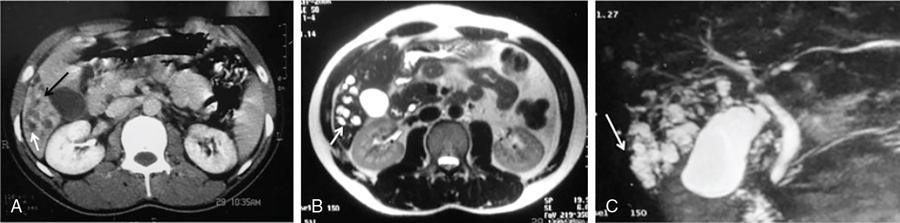

DIFFUSE PARENCHYMAL DISEASES OF THE LIVER Ishan Kumar, Ashish Verma The hepatic parenchyma is the site for multiple essential, interrelated, and complex metabolic activities to assimilate nutrients, detoxify the body, and synthesize vital molecules such as enzymes, hormones, cofactors and essential components of the coagulation pathway. The chemical reactions involved in each of these activities pose a threat to the hepatocytes, which may be damaged leading to the initiation of reparative processes. Further, the liver, being a highly vascular organ with multiple metabolic activities, is liable to be involved in many systemic vascular and metabolic disorders. On one hand, such changes cause healing of the tissue injury, but on the other hand, lead to diffuse parenchymal changes, which may result in suboptimal functioning of the organ. Such a condition is labelled as ‘diffuse liver disease’ and includes (a) diseases caused due to storage of certain chemical products of such chemical reactions labelled as ‘storage disorders’, (b) diseases caused due to reduction of blood flow to the organ, (c) parenchymal injury due to stasis of bile at various levels in the pathway due to varied causes, and (d) involvement of liver in systemic or organ-based inflammatory disorders. The mainstay of diagnosis of diffuse liver diseases is the detection of alterations in the biochemical parameters in blood indicative of liver function, which however is nonspecific to various aetiologies. The diffuse liver diseases in children are quite different from those in the adult population and constitute mainly of congenital or inherited metabolic and vascular diseases as opposed to diseases of acquired aetiologies in the latter population. The gross and microscopic pathological changes are accordingly different in the paediatric population and may be utilized to add specificity to the biochemical indicators as far as aetiological diagnosis is concerned. The invasive and potentially hazardous sampling mandated for histological evaluation of liver parenchyma has been replaced by an array of imaging modalities in recent times. The present chapter presents a review of the currently available imaging modalities (viz. cross-sectional imaging modalities such as ultrasonography, computed tomography [CT] and magnetic resonance [MR] imaging) for evaluation of diffuse liver diseases along with the pertinent imaging features and guidelines for their rational use in various indications. Also a short review of certain key technical and technological details is included. Jaundice and hepatomegaly are the most common clinical manifestations of liver disease. Anorexia is a nonspecific sign, often present in acute or chronic liver disease. Jaundice is a sign of increased bilirubin content in the blood, that can exist in four forms: (i) unconjugated bilirubin bound to albumin, (ii) unbound unconjugated bilirubin, (iii) conjugated bilirubin and (iv) δ fraction. Direct fraction includes both conjugated bilirubin and δ bilirubin. Conjugated hyperbilirubinemia is due to decreased excretion by liver or biliary tract obstruction. Pruritus, spider angioma on face and neck, ascites, portal hypertension, botchy palmer erythema, subcutaneous xanthoma, gastrointestinal (GI) variceal bleed, encephalopathy, renal dysfunction and pulmonary involvement are manifestations of advanced cirrhosis. Evaluation of total serum bilirubin and its fractional analysis into indirect (unconjugated) and direct (conjugated and δ fraction) bilirubin helps to distinguish between elevation caused by haemolysis and that due to hepatic dysfunction or biliary obstruction. Elevations in alkaline phosphatase (ALP), 5′ nucleotidase, and γ-glutamyl transpeptidase (GGT) levels are an indicator of biliary obstruction. However, it should be noted that normal growing children have significant elevations of serum ALP activity. AST (aspartate aminotransferase) and ALT (alanine aminotransferase) are significantly raised in acute hepatitis. ALT rise disproportionate to AST rise is seen in viral hepatitis. A predominant rise in AST is seen in echovirus infection, various metabolic diseases or alcohol-induced hepatitis. These aminotransferases are also elevated in NAFLD/NASH. ALT/AST rise is less marked in chronic liver disease. PT-INR, serum albumin levels can evaluate the hepatic synthesis function. Hypoalbuminemia suggests a bad prognosis. γ-Globulin is elevated in autoimmune hepatitis (AIH). Alpha-fetoprotein is raised in hereditary tyrosinemia or hepatic neoplasms. Indications of liver biopsy in the paediatric age group include neonatal cholestasis, metabolic liver disease, NAFLD, congenital hepatic fibrosis, abnormal biochemical liver tests of unknown aetiology, intestinal failure associated liver disease, acute liver failure and liver tumours. Although biopsy of children and infants is considered a safe procedure, due to incidences of shock, the North American Society for Pediatric Gastroenterology and Nutrition (NASPGHAN) has recommended liver biopsy in children not to be necessarily performed as outpatient procedures. Sonography-guided percutaneous liver biopsy has been reported to be safer, more efficient, more comfortable and only marginally more expensive than blind biopsy. The use of coaxial technique, determination of the number of passes and use of track embolization were at the discretion of the interventional radiologists. In cases of uncorrected PT-INR elevation, transjugular liver biopsy can be performed. Ultrasound (US) is a valuable tool in the diagnosis and management of diffuse liver diseases. It provides useful information about the size, surface, parenchymal architecture, biliary channels and blood flow of the liver. US examination of the liver is performed in the supine position with a convex (5–7.5 MHz) probe. High-frequency (7.5–12 MHz) linear transducers can be used in young infants because of their small size. US examination can be completed with the colour Doppler technique and US elastography, if needed. CT protocol typically requires image acquisition during the multiple phases with a slice thickness of 5 mm or less and a pitch ranging from 1 to 1.5. Contrast injected is 2 mL/kg through manual or mechanical injection. The arterial phase begins at 10–15 seconds and the portal phase is at 20–40 seconds after contrast injection. Equilibrium phase is obtained at 3 minutes, when needed. MRI protocol to evaluate paediatric liver chiefly includes free-breathing sequences, due to the challenge offered by an inadequate breath-hold in these patients. Due to the same reason, motion insensitive single-shot HASTE sequences or motion insensitive T1-weighted spoiled GRE single-shot sequences are also widely utilized in paediatric MR examinations. In slightly older children with a relatively uniform breathing pattern, external trigger signals from a breathing belt, or navigator techniques may be used to overcome motion artefacts from breathing. T1- and T2-weighted turbo spin-echo (TSE) sequences and T2-weighted single-shot sequences in axial and coronal planes are initially acquired to evaluate the anatomy and screen for pathologies. This is followed by a gradient echo (GRE) images to examine vascular structures. Multiecho images with T1-weighting can be acquired to evaluate the fat content of lesions. Contrast-enhanced MRI with intravenous injection of gadolinium (Gd)-based contrast agent is performed as routine in cases with suspected portal hypertension or in any associated suspected neoplastic lesion. This is usually clubbed with MRA for vascular mapping. Arterial phase and portal phase should be acquired 10–15 seconds and 20–30 seconds, respectively after the start of contrast agent injection. GRE T1-weighted sequence should be repeated continuously four or five times to include achieve all phases of liver perfusion. Finally, steady-state imaging should be performed in the equilibrium phase (3 minutes) using T1-weighted and T1-weighted fat-suppressed imaging sequences. MRI contrast media should be administered with caution after evaluation of eGFR, and is safer than the iodinated contrast media needed for CT scan examination, and is hence preferred. Liver size measurement is commonly obtained in one of the two ways (a) an anterior to the posterior measurement of the liver in the midclavicular line, (b) a dome-to-tip longitudinal measurement of the liver in the midclavicular line. Table 9.8.1.1 provides suggested upper limit values of liver and spleen length for various paediatric age groups. Despite advances in 3D US, volume measurements of liver size have not been incorporated in the routine clinical practice because it is time-consuming, requires considerable skill and technically difficult fusion of multiple 3D sweeps. Nonalcoholic fatty liver disease (NAFLD) is referred to as triglyceride accumulation in hepatocytes and encompasses a broad range of clinicopathological entities ranging from simple steatosis, steatohepatitis to cirrhosis. Its worldwide reported prevalence is approximately 2.6%–10% in the general paediatric population and as high as 38% of obese children under the age of 19 years. In India, the reported prevalence is as high as up to 22% in the general paediatric population and up to 45% in obese and overweight children. Hepatic steatosis currently is the most common cause of chronic liver disease in paediatric patients. Table 9.8.1.2 highlights the causes of hepatic steatosis in paediatric age group. The pattern of injury is similar to alcoholic liver disease. Nonalcoholic steatohepatitis (NASH) constitutes a subset of NAFLD, ranging from simple steatosis to inflammation and fibrosis. NASH in children has two distinct histological subtypes. Type 1 NASH resembles adult subtype with macrovesicular steatosis, lobular inflammation, and ballooning degeneration and perisinusoidal fibrosis. Type 2 NASH shows steatosis with portal fibrosis and is present in younger children with increased severity of obesity. ALT can be normal in 20% of the patient with NAFLD and liver biopsy is the gold standard for diagnosis as well as a semiquantitative assessment of disease severity. In clinical practice, the diagnosis and monitoring of NAFLD largely rely on ultrasonography. Grade I fatty liver refers to diffusely hyperechoic parenchyma with a well-visualized diaphragm (Fig 9.8.1). Bright liver with loss of periportal echogenicity and indistinctly visualized vessels is referred to as grade II and blurring of the diaphragm is classified as grade III fatty liver. Limitations of the US are lack of objective quantification and diminished sensitivity in cases where biopsy-proven steatosis ratio is less than 30%. Moreover, hepatic fibrosis and inflammation in cases of NASH are sonographically indistinguishable from simple steatosis. Contrast-enhanced US can diagnose the presence of fibrosis in NAFLD, which is evident from the decreased accumulation of microbubbles in the liver parenchyma. The distinction between hepatic steatosis and fibrosis is important clinically, as fibrosis can progress to cirrhosis if left untreated. US elastography has emerged as a promising technique to screen the children with NAFLD to look for ongoing steatohepatitis/fibrosis. Transient elastography is the most popular elastography technique which has shown excellent accuracy in the adult population with chronic hepatitis. However, its accuracy in NAFLD is significantly lower and the data of effectiveness in the paediatric population is limited. Acoustic radiation force impulse imaging (ARFI) has been shown to have a good correlation with AST/ALT ratios in obese children with NAFLD. An ARFI elastography value of >1.19 m/s predicts NASH-related hepatic changes in these patients while a value >1.75 m/s is suggestive of cirrhosis. Another study on shear-wave elastography has shown a high correlation in paediatric NAFLD patients with biopsy-proven hepatic fibrosis. A value of >5.1 kPa strongly predicts the presence of fibrosis whereas a value of >6.7 kPa is suggestive of stage ≥F2 fibrosis (Brunt scoring system). CT is a common modality utilized for assessment of hepatic pathologies, however is seldom used for assessment of NAFLD because of the risk of ionizing radiation. On noncontrast CT, liver attenuation <40 HU or hepatic attenuation 10 HU lesser than that of the spleen is considered as a sign of steatosis. Recent literature advocates the utilization of MRI in the evaluation of NAFLD. Fat imparts high signal intensity to the liver parenchyma on T1-weighted spin-echo MR images while it is mildly hyper- to hypointense on T2-weighted images. Conventional spin-echo imaging is relatively insensitive to mild-to-moderate fatty infiltration of the liver. The most commonly employed technique for detection of steatosis is chemical shift imaging (Dixon technique or dual-echo method) which utilizes two sets of gradient-echo images of the liver, that is in-phase and out-of-phase. On in-phase echo-time, water and fat signals add whereas, on out-of-phase echo-time, water and fat signals cancel each other. In nonfatty livers, the signal intensity of the liver parenchyma is unchanged between in- and opposed-phase images whereas a fatty liver shows a notable reduction of signal intensity on the opposed-phase images. Iron deposition in the liver can interfere with the assessment of steatosis. MR spectroscopy has been one of the most reliable techniques for the evaluation of hepatic steatosis (Fig 9.8.1.2). Protons in water molecules resonate at 4.7 ppm while that in triglyceride molecules resonate predominantly at 1.3 ppm. Other smaller lipid peaks can be obtained at 0.9, 2.0, 2.2 and 5.3 ppm. In a healthy nonfatty liver no triglyceride peak should be present. The presence of fat can allow measurement of area under water peak versus area under fat peaks to procure hepatic fat fraction. Proton density fat fraction (PDFF) measurement by MRI is another promising objective technique for quantification of steatosis in the paediatric patient. PDFF is the ratio of the density of mobile fat protons and the total density of protons including that from triglycerides and mobile water. Magnetic resonance elastography (MRE) is suggested as a noninvasive tool to evaluate liver stiffness that correlates with the degree of fibrosis. The technique is based on measuring the propagation of shear waves through liver parenchyma. A cut-off value for liver stiffness of 2.27 kPa has been suggested to predict Ludwig grade 2 or higher fibrosis. The technique depends on measuring the propagation of shear waves through the hepatic parenchymal fibrosis and differentiation of low-grade fibrosis from high-grade and also it may be feasible to distinguish steatosis from steatohepatitis. Success rate and accuracy of MRE is higher than US-based transient elastography. Cirrhosis is referred to as diffuse end-stage chronic liver disease characterized histologically by fibrosis and nodular regeneration, along with the disorganization of liver architecture. Although various underlying aetiology can lead to cirrhosis in children (Table 9.8.1.3), the most common causes in India are posthepatitic cirrhosis, Wilson’s disease (WD), AIH, biliary cirrhosis, biliary atresia and other metabolic diseases. In 5%–15% cases, the cause of cirrhosis may remain undetermined and is known as cryptogenic cirrhosis. Imaging is central to the diagnosis and management of children with cirrhosis (Fig 9.8.1.3). The role of imaging extends from diagnosis of cirrhosis to identification of complications and detection and characterization of nodules in cirrhotic liver. The imaging findings consist of changes in liver morphology, parenchyma and contour of the liver, vascular changes including portal hypertension, liver nodules and other complications of cirrhosis. Cirrhosis can lead to volume redistribution, which can be evaluated using either the US, CT, or MRI. Signs of early cirrhosis are atrophy of the segment IV, evident on imaging by increased fat segment IV and portal vein and between segment IV and left lobe. Signs of advanced cirrhosis are atrophy of the right lobe and segment IV with compensatory hypertrophy of left lobe and caudate lobe and fatty expansion of GB fossa. In some patients, a sharp notch is seen in the posterior surface of the liver (segment VI/VII). Some aetiology of cirrhosis may have different patterns of volume redistribution such as atrophy of left lobe and posterior segments in primary sclerosing cholangitis, diffuse hypertrophy in primary biliary cirrhosis, and absence of caudate hypertrophy in WD. The US can detect changes in liver segmental volumes based on linear measurements. C/RL (caudate/right lobe) ratio >0.65 calculated by comparing the transverse length of caudate and right lobe at the portal bifurcation, is a sign of cirrhosis. CT/MRI-based segmental volumetric analysis can reflect the morphological changes more effectively. Liver parenchyma in children appears as isoechoic to hypoechoic compared to the renal cortex in the US. The neonatal liver may reveal a bright echotexture. Hyperechoic parenchyma is seen in the fatty liver or liver fibrosis. Cirrhosis is seen as coarse and heterogeneous parenchyma. The liver surface in normal children appears as a hyperechoic, straight and regular line. The liver surface with diffuse irregularity or nodular surface is present in cirrhosis. CT and MRI in frank cirrhosis can reveal heterogeneous parenchyma along with the irregular surface. Diagnosis of early cirrhosis and fibrosis cannot be reliably made by the US where parenchyma may appear within normal limits. Similarly, CT and conventional MR sequences are also insensitive in early cirrhosis although early fibrosis can be seen as T1 hypointense/T2 hyperintense areas on MR and may show subtle enhancement. These T2 hyperintensities can be present as perilobular bands, perivascular cuffing, bands surrounding regenerative nodules, patchy fibrotic areas, or diffuse reticulation (honeycomb pattern). The role of US elastography and MR elastography is increasing in paediatric liver diseases for the detection of fibrosis and early cirrhosis and has been discussed in the previous section. US examination should be complimented with Doppler of the portal vein and hepatic veins if US features are suspicious of cirrhotic or fibrotic changes. The diameter of the portal vein increases with age. The mean diameter of the portal vein is 3.5 mm in children <5 years, 6.3 mm in 6–12-year old children, and 7–11 mm in >12-year-old children. Portal vein diameter is increased in portal hypertension; however, no reliable age-dependent cut-off values exist for the PV diameter in the diagnosis of portal hypertension in paediatric patients. Peak portal vein velocity in the paediatric age group is usually above 20 cm/s in a nonfasting child (15 cm/s in term neonate) along with some respiratory undulation. Peak portal vein velocity <16 cm/s in the paediatric age group is suggestive of portal hypertension. In term neonates, the values are above 15 cm/s. An increase in pulsatility of the portal vein (PI < 0.5) suggests portal hypertension. Reversal of portal vein flow (hepatofugal flow), presence of periportal collaterals or portal cavernoma, umbilical vein recanalization and various other collaterals are other signs of portal hypertension. Hepatic veins should be evaluated to rule out Budd–Chiari syndrome. CT or MR portal venography can comprehensively assess the extent and anatomical location of portosystemic collateral vessels in children with liver cirrhosis. Four groups of collateral channels can be identified: (a) periportal collaterals and portal cavernoma, (b) collaterals draining into SVC, that is left gastric vein (coronary vein), short gastric vein, oesophageal and paraoesophageal collaterals, (c) collaterals draining into IVC such as paraumbilical vein and abdominal wall collaterals, splenorenal and gastrorenal collateral, (d) mesenteric, retroperitoneal and haemorrhoidal collaterals. Various nodules can be seen in the cirrhotic liver including regenerative nodules, dysplastic nodules and HCC. The US is not sensitive in identifying these nodules and high-frequency linear-array transducer can contribute to their detection. CT and preferably MR can be used to characterize these nodules. Table 9.8.1.4 summarizes the imaging findings of these nodules on CT and MRI. It should be noted that HCC is rare in young children although it has been reported in children younger than 5 years in progressive familial intrahepatic cholestasis (PFIC) and Byler disease, biliary atresia. Recognizing the need for paediatric-specific guidelines for standardized interpretation and reporting CT and MR, ACR – LI-RADS (Liver Imaging Reporting and Data System) committee has convened the Pediatric LI-RADS Working Group in 2017. Hepatorenal fibrocystic diseases (HRFCDs) are developmental abnormalities of the liver and portobiliary system with associated fibrocystic degeneration of the kidneys. HRFCDs belong to the larger group of disorders collectively referred to as ‘ciliopathies’ a term describing the group of disorders affecting primary cilia which are an organelle present within the cholangiocytes. The ciliopathies in the liver is manifested as ductal plate malformation. Ductal plate is the embryonic precursor of the intrahepatic bile ducts and their abnormal development leads to cyst formation and alteration in portal venous development. Two major disorders are included in these malformations: (i) congenital hepatic fibrosis (affecting small intrahepatic ducts) and (ii) Caroli’s disease (affecting larger ducts). A combination of the CHF and CD is known as Caroli’s syndrome. Liver function test results in DPM may remain normal or be only modestly elevated. Few of congenital cystic liver pathologies are not associated with ciliopathies, such as autosomal-dominant polycystic liver disease (ADPLD) and portal fibrosis associated with congenital disorder of glycosylation (CDG) type Ib. Tables 9.8.1.5 and 9.8.1.6 innumerate the renal diseases and syndromes associated with ciliopathies. Carbohydrate-deficient glycoprotein syndrome type 1b Renal–hepatic–pancreatic dysplasia Oral–facial–digital syndrome type I US is the first-line modality, which can detect the distinctive morphological features of CHF that includes left lobe (segments II and III) hypertrophy, normal or hypertrophies segment IV, and atrophied right lobe. Preservation of the volume of the left medial segment is a feature that distinguishes CHF from cirrhosis resulting from viral hepatitis. The US can also detect changes in parenchymal echotexture, presence of splenomegaly, and can identify the evidence of cystic disease in the kidneys. Portal hypertension is one of the common presenting features of CHF despite normal hepatic lobular architecture and normal hepatic function. Application of the Doppler technique can detect the features of portal hypertension and cavernomatous transformation of the portal vein which can be present in up to 50% of the cases of DPM. The portal vein shows abnormalities in its ramification pattern with numerous, hypoplastic branches which are closely spaced, referred to as ‘pollard willow’ pattern. Studies have also shown enlarged hepatic artery and regenerative nodules in the arterialized hepatic parenchyma. In cases of Caroli’s syndrome, the US can easily identify cystic lesions or dilated intrahepatic bile ducts and can detect the stones in the ducts. Intraductal bridging (echogenic septa) can be seen traversing the dilated biliary duct lumen. Occasionally, the US can identify small portal venous branches surrounded by dilated biliary duct. Because of the absence of risks of ionizing radiation, US is the modality of choice in these children for long-term follow-up. CT can comprehensively demonstrate the morphological changes of CHF. Segmental computer-aided volumetric analysis of the hepatic parenchyma can identify the volume distribution with higher accuracy compared to the US. CT can also detect the parenchymal changes with higher sensitivity than the US. CT in these patients shows heterogeneously enhancing liver parenchyma, volume changes, and complete vascular mapping of the abdomen in cases of portal hypertension, identifying the portosystemic collaterals. Periportal cuffing can be identified on CT, indicative of periportal fibrosis. In Caroli’s disease, CT shows segmental and noncontinuous, saccular or fusiform dilatation of intrahepatic biliary radicals with the central enhancing dot representing portal vein branches (Fig 9.8.1.4). CT can identify the communication of the cyst with IHBD, differentiating them from PCLD. CT can also better detect the complications of CD such as cholangitis abscesses and cholangiocarcinoma. Seven per cent of the patients of CD can develop cholangiocarcinoma. MRI and MRCP seem to be a sensitive method for revealing biliary and renal abnormalities associated with congenital hepatic fibrosis and CD, even when sonography findings are normal (Fig 9.8.1.5). The parenchymal changes and heterogeneous architecture along with periportal fibrosis can be demonstrated on T2-weighted images, revealing hyperintensity along the portal vein and its branches. Regenerative nodules can be identified on T2-weighted and contrast-enhanced MRI. MRCP can delineate the communication between the cystic lesions and the biliary tree in cases of CD. Contrast-enhanced MRI can aid in the detection of complicating malignancies which can have a wide range of radiological appearances such as focal hepatic mass, intraductal mass, or biliary stricture. Multiplanar capability of MRI can enable its utility for preoperative planning in the affected children obviating the need for invasive preoperative cholangiogram to demonstrate the anatomy of the biliary tree. The differential diagnosis of Caroli’s disease is ADPLD, Von Meyerberg complex, choledochal cyst, sclerosing cholangitis, recurrent pyogenic cholangitis and peribiliary cysts. PCLD is seen on imaging as more than 20 round and smooth cysts without any communication with the biliary tree. Biliary hamartoma (Von Meyerberg complex) are seen as multiple/unique round uniform small cysts measuring 1–3 mm located close to portal tracts. Recurrent pyogenic cholangitis presenting with intra- and extrahepatic biliary dilatation is the most difficult diagnosis to exclude on imaging, however, the presence of saccular dilatation favours the diagnosis of Caroli’s disease. It should be noted that up to 20% of the cases of Caroli’s disease may have associated extrahepatic bile duct dilatation mimicking choledochal cyst and Caroli’s disease may even coexist with choledochal cyst. The presence of diffuse fusiform dilatation of the extrahepatic duct with less than 3 cm diameter combined with the characteristic intrahepatic ductal findings may help differentiate patients with Caroli’s disease from patients with a choledochal cyst associated with intrahepatic biliary dilatation. Routinely 1–2 mg of iron is absorbed by the intestine in a healthy child. Iron is recycled by extravascular haemolysis in the liver to meet the required amount (25 mg) in the spleen and bone marrow through Kupffer cells. Excess iron is bound to ferritin and hemosiderin in the hepatocytes. Excess iron in the body may be deposited in the liver, spleen, lymph nodes, pancreas, kidneys, pituitary, myocardium and GI tract. Up to 10–20 mg of excess iron does not cause tissue damage, in which case the term haemosiderosis is applied. Functional and structural impairment of the tissues occurs if the iron load (50–60 g) exceeds the compensatory mechanisms. In these cases, the term hemochromatosis is applied. Primary hemochromatosis is a genetic disorder occurring through mutation in the HPE gene which causes increased absorption of iron through the intestine. The secondary nongenetic form is more common and is caused due to multiple blood transfusions (transfusional haemosiderosis) in haematological disorders such as myelodysplastic syndrome, aplastic anaemia, beta-thalassemia major (transfusion haemosiderosis). Prolonged and excessive iron deposition can lead to endocrine abnormality, cardiac failure and liver parenchymal disease. Liver biopsy was considered as a reference standard for the detection and quantification of iron overload in hepatic parenchyma. However, it is largely replaced by radiological techniques because of the invasive nature and small size of sampled tissue while doing a single-site biopsy. The US cannot detect the features of iron overload in the liver parenchyma; however, it can be useful in detecting the complications of iron overload such as cirrhosis, hepatocellular carcinoma (HCC) or features of portal hypertension. CT scan is also of limited utility in hemochromatosis. Attenuation of >65 HU (15–130) with low attenuation of hepatic vessels relative to liver parenchyma on noncontrast CT is suggestive of iron overload, however can also be seen in WD, glycogen storage disorder, long-term amiodarone administration. MRI is the primary radiological modality used for diagnosis of iron distribution, quantification and monitoring of treatment response in liver iron overload (Fig 9.8.1.6). Various MRI techniques have been devised for iron overload estimation. This technique compares the signal intensity of liver parenchyma with the signal intensity of paraspinal muscles, which are assumed to be unaffected by iron content. GRE sequences are obtained with TR of 120 ms, flip angle 200, and varying TE of 2, 4, 9, 14 and 20 ms. Three ROIs of 1–2 cm are drawn in liver parenchyma and one on each paraspinal muscles. Liver iron concentration can then be obtained using a free online calculator provided by the University of Renne. Images are obtained with TR 2500 ms, flip angle 900 and variable TE of 6, 9, 12, 15, 18 ms. The images can be used to draw automated ROI covering the right lobe of the liver (excluding vessels) in the largest area and a T2 map of the same images can be generated. The technique quantifies the T2 shortening due to proton exchange between bulk water and exchangeable protons in ferritin. T2* takes into account the contributions of the T2 (1/R2) effects and the microscopic inhomogeneities introduced in (B0) by the hemosiderin clusters. For T2* measurement single breath-hold multiecho GRE sequences with TR of 25 ms, flip angle of 20 degrees, TEs every 0.25 ms from 0.8 to 4.8 ms are obtained. R2 * (1/T2*) values can be generated with ROI drawn from a single midhepatic section by drawing an ROI following the boundaries of the liver and excluding hilar vessels. Liver iron concentration can be obtained using a formula: [Fe] = 0.202 + 0.0254 R2*. This technique detects the enhancement in the local magnetic field caused due to ferritin or hemosiderin using a 3D breath-hold multiecho GRE sequence with the use of chemical shift–encoded water/fat separation, T2*/R2* mapping, and B0 field mapping. A quantitative susceptibility map of the parenchyma is generated. A local relative susceptibility value (ΔB0) is obtained drawing ROI which is expressed in parts per million (ppm), related to local iron deposition. With the ongoing research, stress is being placed upon the multiparametric quantitative MR imaging protocol which includes MR elastography (for fibrosis), multiecho chemical shift–encoded GRE to measure proton-density fat fraction (for steatosis quantification) and R2* relaxometry (for iron overload estimation). Hepatic iron overload has been shown to predispose to the development of HCC in the younger age group. The detection of HCC in the setting of iron overload is less difficult on T2-weighted sequences because the presence of iron behaves like a nonspecific contrast medium, such as superparamagnetic iron oxide (SPIO). However, care should be taken while evaluating these lesions, which may appear like hepatic cyst or haemangioma. Any nodule detected in these patients should be evaluated and characterized by the use of intravenous gadolinium contrast. The liver processes various metabolic processes of the body and hence it can be affected by multiple inherited metabolic disorders. The affection of the liver in these disorders may be in the form of hepatomegaly, cholestasis, acute liver failure or hepatic encephalopathy. WD is an autosomal recessive disorder of copper metabolism, first described in 1912 by Samuel Kinnier Wilson. The primary defect is a genetic abnormality located at chromosome 13 and q14.3, coding for copper-transporting P-type ATPase. An average diet contains 3–5 mg copper, 40% of which is absorbed in the upper GI tract and which is almost completely excreted in bile. The genetic defect leads to abnormality in this excretory function that leads to copper accumulation in the liver and other organs and tissues including brain and cornea. Liver disease in WD can range from asymptomatic transaminasemia, acute or chronic hepatitis, fulminant hepatic failure, and cirrhosis. WD can be misdiagnosed as AIH because both can result in similar autoantibodies. Imaging findings of liver manifestations can be categorized into four groups: (i) morphological changes, (ii) parenchymal changes, (iii) perihepatic changes, (iii) other findings. On CT, copper deposition in the liver may present with increased attenuation of the hepatic parenchyma, however, associated hepatic steatosis can decrease the overall attenuation which is within normal limits in most of the patients. Contrast-enhanced CT can show hypodense as well as hyperdense nodules and surface irregularity. The disappearance of hyperdense nodules has been documented after penicillamine therapy. Various MRI features of liver disease in WD has been described in the literature that includes (a) T1 hyperintense/T2 hypointense nodules (2 mm to 1 cm), (b) T1 hypointense nodules, (c) multiple hyperintense septae leading to ‘honeycomb pattern’, (d) high-intensity septa, (e) absence of parenchymal changes on MR. 31P MR spectroscopy of the liver in WD can show elevated phosphomonoester (PME) resonance and reduced phosphodiester (PDE) resonance, which have been shown to normalize after penicillamine and vitamin K therapy. Gaucher disease (GD) results from a deficiency of lysosomal enzyme β-glucocerebrosidase leading to the accumulation of ‘Gaucher cells’ in various organs. Imaging can help in the detection and characterization of liver infiltration, hepatomegaly, fibrosis, cirrhosis, iron deposition and HCC, all of which are associated with GD. On imaging, hepatosplenomegaly is the hallmark of GD (Fig 9.8.1.7). Recent literature recommends the utilization of CT or MRI over the US for volumetric assessment of liver and spleen sizes in GD with the expression of liver volume as multiples of normal volume (MN). Weight-based formula is used for calculation of liver and spleen volumes: normal liver volume (mL) = 25 × weight (in kg) ; and normal spleen volume (mL) = 2 × weight (in kg). A target liver volume of 1–1.5 MN and a spleen volume of 2–8 is aimed by the therapeutic regimens. On MRI, low ADC of liver and spleen indicates greater infiltration and worse prognosis, with ADC values correlating with chitotriosidase levels. Fibrosis can be detected and quantified using US shear-wave elastography, MR elastography, and nonimaging–based transient elastography. Studies have indicated the presence of liver iron deposition in GD due to associated hyperferritinemia, which can be quantified using R2* relaxometry. Hepatic nodules can be identified on imaging on GD. Most commonly these nodules represent a focal accumulation of Gaucher cells and are known as ‘Gaucheroma’. These lesions are hyperechoic on the US, hypoattenuating on CT, T1 hypointense/T2 heterogeneous nodules on MRI. These lesions do not merit biopsy; however, care should be taken to identify the lesions suspicious for HCC, that is large, irregular, hypoechoic, hypervascular lesions, which mandate further evaluation by multiphasic contrast CT or MRI. Besides the liver, evaluation of abdominal imaging should attempt to detect changes in spleen and visualized bones. GD in the spleen can manifest with splenomegaly, fibrosis, nodules, subcapsular infarcts and splenic necrosis. Osseous features of GD are osteopenia, osteonecrosis, pathological vertebral fractures and Erlenmeyer flask deformity. These are a group of disorders caused by defects in metabolism or storage of glycogen which broadly present with hepatic, myopathic, cardiac or other manifestations. GSD type I (Von Girke disease) presents with hepatic involvement. The US in these patients shows hyperechoic liver parenchyma because of fatty replacement and glycogen deposition. CT shows variable attenuation because hepatic attenuation is increased by glycogen and decreased by steatosis. There is a well-known association with GSD and hepatic tumours such as adenoma, focal nodular hyperplasia and HCC (rare). Adenomas are the most common tumours in GSD which show variable echogenicity. These lesions may contain fat, haemorrhage, or rarely dystrophic calcifications. A fat component can be detected using chemical shift MRI. These lesions should be monitored serially and malignancy should be suspected in case of rapid growth. α1-Antitrypsin deficiency is a rare autosomal recessive disorder that can cause chronic severe paediatric liver disease. In infants, this disorder can have a presentation similar to biliary atresia or idiopathic neonatal hepatitis. Moreover, scintigraphy cannot distinguish between biliary atresia, because similar to atresia, it can show uptake by hepatocytes and absence of biliary excretion due to paucity of lobular biliary ducts. The US in the neonatal period can help distinguish between the two, as it shows normal gallbladder and hepatic parenchyma. Older children may show imaging evidence of hepatic fibrosis or cirrhosis. MR elastography in this disorder is accurate for identifying fibrosis with a cut-off value of >3 kPa predictive of fibrosis. Various systemic illnesses can present with liver disease. The table summarizes the hepatic manifestations of various systemic liver diseases. TABLE 9.8.1.7 Paediatric diffuse liver diseases though forming a small subset of overall morbidity in children pose a formidable challenge for diagnosis as most cases present at a relatively early age. Imaging in these cases aims to make an aetiological diagnosis and rule out any associated complications, as the initial diagnosis is usually established by the biochemical analysis of liver function. Screening sonography usually forms the initial screening modality with MRI being the next stop problem-solving modality. CT scan has taken a back seat in current practice due to radiation exposure and the need to inject iodinated contrast media, both of which can be obviated by MRI. The former modality however remains essential in case an interventional procedure to treat portal hypertension is contemplated or percutaneous sampling from areas difficult to access by sonography is to be done. With the availability of an array of imaging modalities, it remains essential for an imaging expert to be clear as far as the choice of modality and order of its usage during the course on management is involved so that the most optimum imaging protocol can be offered to the patient. PEDIATRIC BENIGN HEPATIC MASSES (INCLUDING INFECTIONS) Kushaljit Singh Sodhi, Anmol Bhatia, Akshay Kumar Saxena Liver neoplasms constitute around 2% of all neoplasms seen in the pediatric population, and around 6% of the total abdominal neoplasms. Only one-third of the liver tumours in children are benign, while two-thirds are malignant. Benign hepatic tumours in children include lesions which are specific to children like mesenchymal hamartomas and vascular tumours, and the lesions that are also seen in adult population, such as adenoma, focal nodular hyperplasia (FNH) and nodular regenerative hyperplasia (NRH). Further, benign hepatic lesions affecting children include a wide variety of infections of bacterial, fungal and parasitic origin. In the present chapter, we will be discussing about the benign hepatic tumours and hepatic infections commonly seen in the pediatric population. A wide variation has been reported in the use of terminology for the hepatic vascular malformations in literature. According to the standard nomenclature adopted by the International Society for the Study of Vascular Anomalies (ISSVA), liver vascular tumours in children are termed as liver hemangioma. Liver hemangiomas in children are classified as infantile and congenital. Infantile hemangiomas usually begin to grow after birth, continue to grow during the first year of life and enter an involuting phase between 1 and 7 years. These tumours are positive for glucose transporter-1 protein (Glut-1), a protein that facilitates the transport of glucose across erythrocyte cell membranes. On the other hand, congenital hemangiomas are fully developed at birth and are characterized by Glut-1 negativity. These are further subdivided into a rapidly involuting group and a noninvoluting group, with some overlap between these groups. Hemangioma is a model of the angiogenesis concept proposed by Folkman et al and its development is related to a combination of upregulation of factors that promote angiogenesis and downregulation of its inhibitors. Most of these tumours are diagnosed in the first year of life, with these being slightly more common in females. Most commonly, these present as an asymptomatic mass in abdomen; however, associated life-threatening presenting complications have also been reported. These include high-output cardiac failure as a result of large arteriovenous shunts or Kasabach–Merritt syndrome of coagulopathy, severe hypothyroidism and acute hemoperitoneum due to tumour rupture. Lesions can be focal, multifocal or diffuse. Multifocal lesions are usually small and homogenous in appearance, while larger lesions may show areas of hemorrhage, calcification, fibrosis and necrosis. The liver is grossly enlarged in diffuse disease, which may cause mass effect on surrounding organs and vessels. Multifocal lesions frequently are associated with multiple cutaneous infantile hemangiomas with a Glut-1 positive marker. Biopsy of these masses should be avoided as there is a risk of bleeding, and the diagnosis is made based on typical imaging features and involution at follow-up. Well-defined hypoechoic or hyperechoic lesion, which may show heterogenous echotexture because of central hemorrhage/necrosis. A variety of flow patterns may be seen on colour Doppler due to the presence of shunts which may be portosystemic, or arteriovenous shunts. The hepatic arteries and veins usually enlarged, with large feeding arteries and draining veins seen surrounding as well as within the lesions. The lesions are usually hypoattenuating to the liver parenchyma with speckled calcifications seen in up to 50% of cases. The enhancement pattern is similar to that of hemangioma in adults and shows intense peripheral nodular enhancement on arterial phase with progressive centripetal filling on venous and delayed phases. Small lesions usually show intense and uniform enhancement (Fig. 9.8.2.1). The lesions show hypointense signal on T1-weighted images (T1WI) and hyperintense signal on T2-weighted images (T2WI). The tumour shows internal vascular flow voids and centripetal enhancement (Fig. 9.8.2.2). Heterogeneous signal may be seen due to presence of hemorrhage, thrombosis and necrosis. Calcifications may be seen in about 16% of cases.

Fibrocystic liver disease